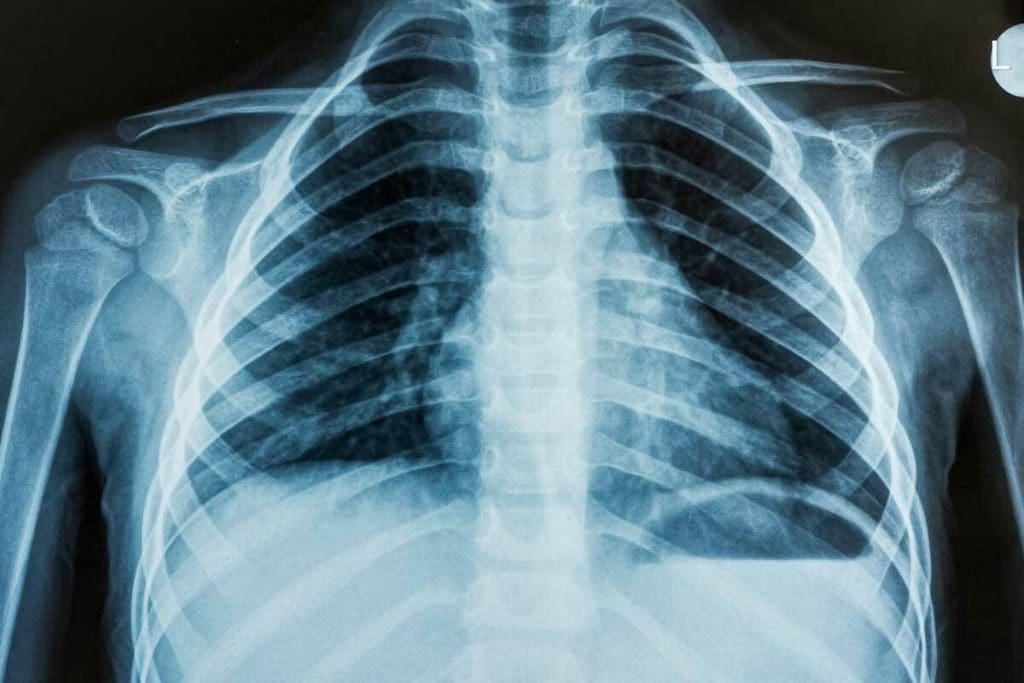

What Is an X-Ray? Understanding the Basics

The X-ray is a key tool in healthcare today. It helps us see inside the body. This is important for diagnosing and treating many health issues.

How X-Ray Technology Works

X-rays use electromagnetic waves to show us what’s inside the body. When an X-ray beam hits the body, different parts absorb it differently. For example, bones absorb more than soft tissues. This makes it possible to see detailed images of the body’s inside.

Common Applications in Medical Diagnosis

X-rays are used a lot for checking bones, lungs, and teeth. They are great for:

- Spotting bone problems like osteoporosis and fractures.

- Finding lung infections like pneumonia.

- Looking at dental issues, like cavities and abscesses.

We also use X-rays to help with some medical procedures. This includes putting in catheters or fixing broken bones.

Understanding X-rays and their uses shows their importance in healthcare. They help us check bone health and lung conditions. X-rays are a basic but essential tool in medicine.